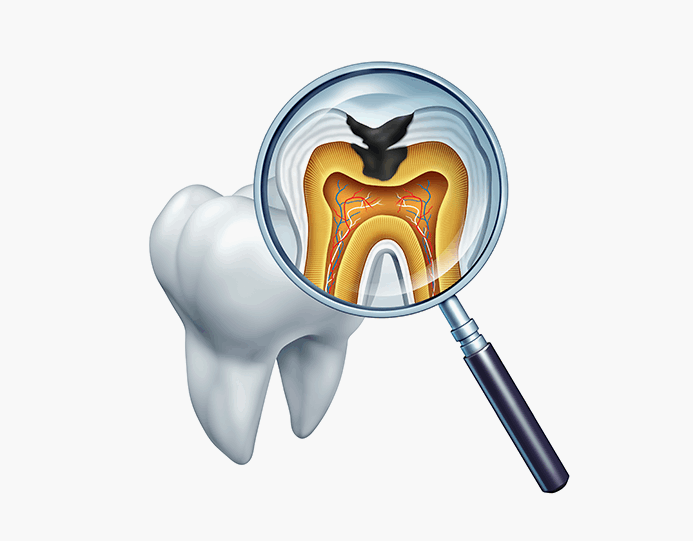

신경치료는 충치가 신경까지 번진 경우, 치아가 부러져 신경이 노출된 경우, 뿌리에 염증이 생긴 경우 진행하는 치료방법입니다. 신경관이 막혀있거나 신경관에 post가 박혀있는 경우 치료의 난이도는 매우 어려워 지며 많은 분들이 발치를 권유 받습니다. 청담뷰치과는 자연치아살리기 진료를 전문적으로 다뤄왔기에 막힌 신경관을 찾거나 만곡이 심한 신경관을 다루는 치료까지 성공적인 결과를 제공해 드릴 수 있습니다.